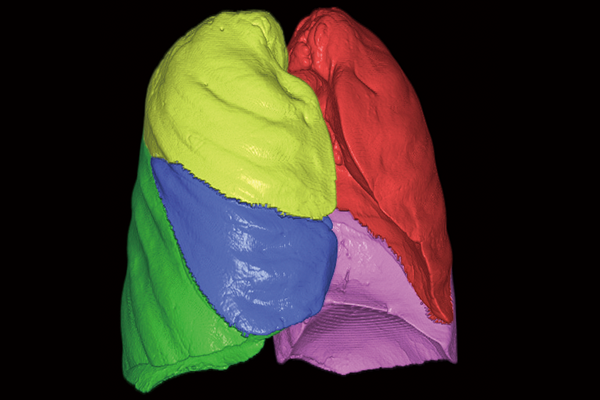

SYNAPSE 3D’s advanced image analysis technology aids clinical interpretation, reporting, and treatment planning. Especially,

automatic organ segmentation technology enables fast and effective workflow, powered by REiLI, FUJIFILM's AI brand. With

a series of high-tech applications developed in collaboration with clinical specialists, SYNAPSE 3D quickly and accurately

delivers imaging result that promotes effective care collaboration.

REiLI makes it happen to extract organs and simplify your work.

Lung lobe